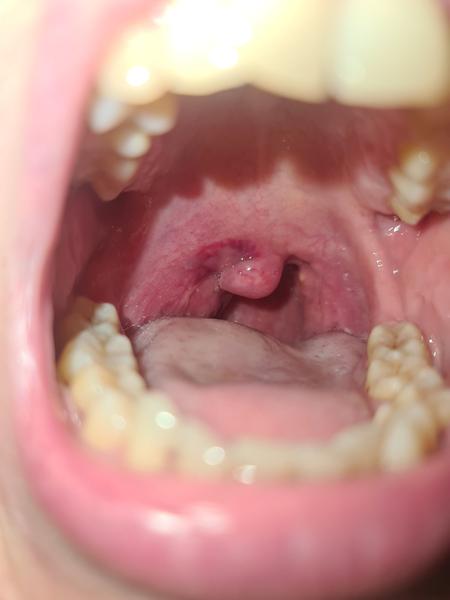

Od stredy beriem antibiotiká, no mám pocit, že vôbec mi nezaberajú...dneska som mala kontrolu, zatiaľ neobsahuje hnis...pripojim fotky...1. fotka dnes, 2. včera

@anonym_autor Ta 1.fotka je horsia ako 2. cize sa to asi zhorsuje. Kto to videl? Obvodny ci ORL? Kazdopadne, absces sa musi riesit narezanim, antibiorika nestacia... Ak to videl len obvodny, isla by som uz dnes na ORL...